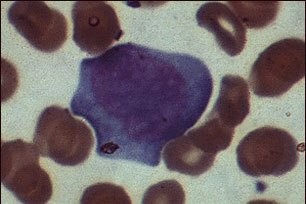

This so-called "Downy cell" is typical of lymphocytes infected by EBV (Epstein Barr Virus) or CMV (Cytomegalovirus) in infectious mononucleosis. Downy cells may be classified as types I, II, or III. This is a type II Downy cell.